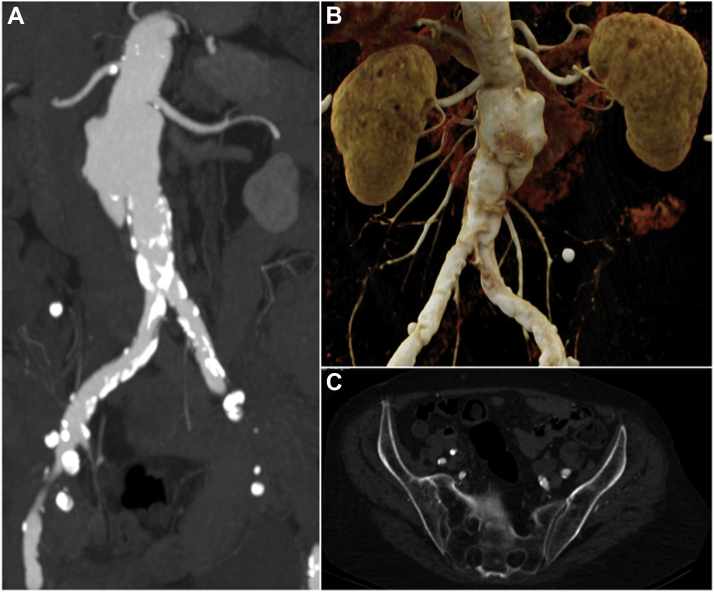

Fig 1.

Anatomic characteristics influencing treatment decisions. Maximum intensity projection (A) and cinematic volume rendering technique (B) images of the juxtarenal aneurysm in correlation with the renal arteries. C, Note the highly calcified and stenotic iliac vessels, with the largest diameter of the right and left external iliac artery being 5 mm and 6 mm, respectively.

Given this anatomic situation (Fig 1), the potential for EVAR as a salvage regimen would have required a fourfold fenestrated stent, with the need for an additional surgical conduit to access the pelvic area because of the calcified stenosing pelvic axis of both and the chronic dissection membrane of the left common iliac artery. Alternatively, an endobronchial prosthesis with a thoracic proximal landing area could have been used. Nevertheless, EVAR carries a high risk of stent graft infection, making this technique a rather experimental approach for C. septicum aortitis. To date, long-term survival (>1 year) after EVAR was achieved for two patients.14,18 Future studies are needed to address the use of EVAR as definitive treatment or a bridge to definitive open surgery for C. septicum aortitis because no sufficient long-term data are available on this topic.